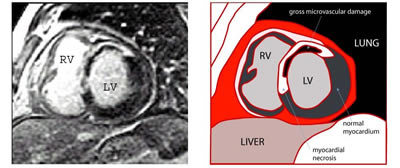

The delayed enhancement (DE) of infarcted areas can help to differentiate between viable tissue, necrotic tissue and the gross microvasculature damage with hemorrhage (see Fig. 1) which is seen as a darker area within the infarcted region (3) (Fig 1).

Figure 1: MR image obtained using the delayed enhancement technique after contrast agent administration. Short axis of the left ventricle of a patient with acute myocardial infarction (three days before). The image shows a large anterior myocardial infarction (white area) and the inner large no-reflow area (dark area). LV = left ventricle, RV = right ventricle.